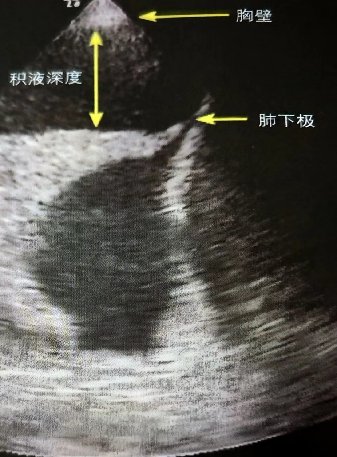

积液容量:在肺底或第5肋间隙水平测量(图11)。距离肺下极3 cm处测量积液深度。积液深度>5 cm提示胸腔积液>500 ml。

图片

图11  胸腔积液深度的超声下测量